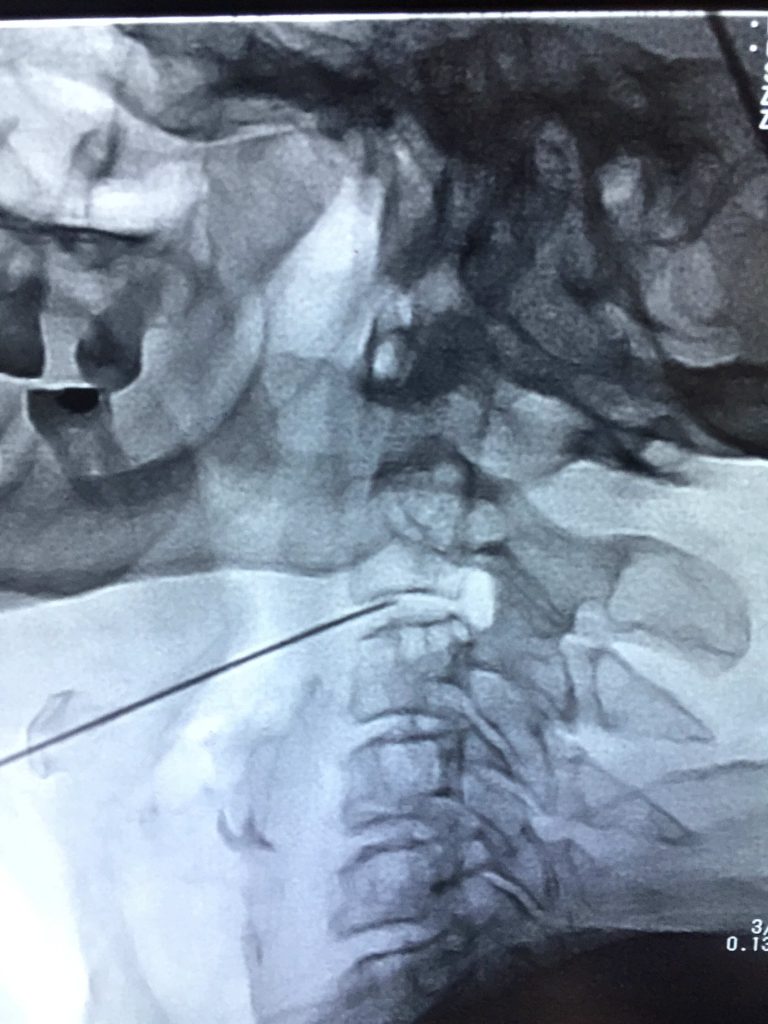

Ozone Therapy (Disc Problems) Overview

Ozone therapy is an innovative treatment that has shown promising results in treating disc problems. This therapy involves injecting ozone gas into the affected area to reduce inflammation and improve blood circulation, thereby promoting the natural healing process. The benefits of ozone therapy are numerous and it is considered an excellent and safest alternative to traditional treatments such as surgery or medication. With its non-invasive approach, it is becoming a popular choice among patients seeking long-lasting relief from disc problems. If you are interested in exploring ozone therapy as a treatment option, please consult with a licensed healthcare professional before proceeding. Their expertise will be key in determining the most effective course of action for your unique case.

Health Tips & Info